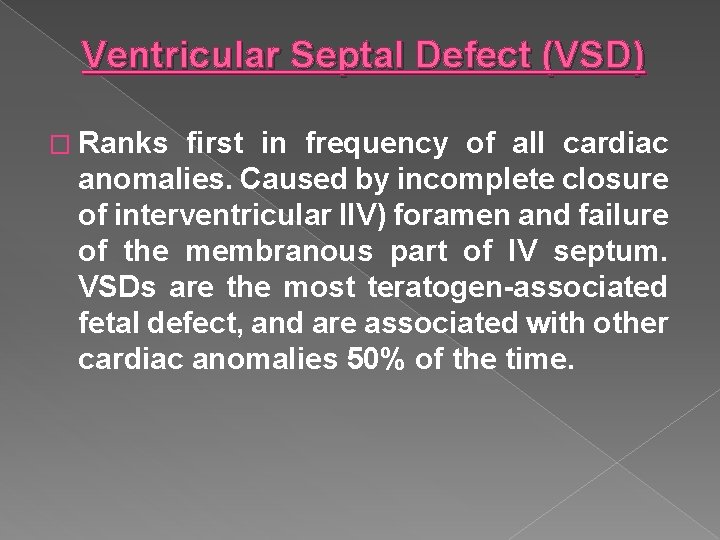

Ventricular Septal Defect (VSD) � Ranks first in frequency of all cardiac anomalies. Caused by incomplete closure of interventricular IIV) foramen and failure of the membranous part of IV septum. VSDs are the most teratogen-associated fetal defect, and are associated with other cardiac anomalies 50% of the time.

�A ventricular septal defect (VSD) is a defect in the ventricular septum, the wall dividing the left and right ventricles of the heart. � Congenital VSDs are collectively the most common congenital heart defects.

Ventricular septal defect (VSD) › Ranks first in frequency of all cardiac anomalies › Opening between the two ventricles › Commonly caused by a teratogen-associated fetal defect. › Associated with other cardiac anomalies 50% of the time. › Seen by demonstrating an opening between the ventricles on a 4 chamber view